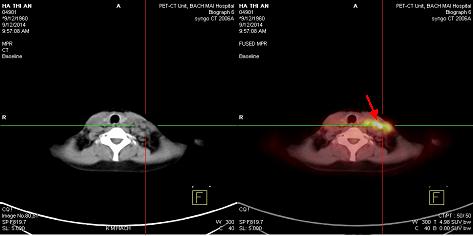

Bệnh nhân được chụp PET/CT nhằm mục đích đánh giá giai đoạn bệnh cho thấy: Hình ảnh tăng hấp thu dược chất phóng xạ tại hạch thượng đòn trái, thành dạ dày, cổ xương đùi phải, và hạch ổ bụng.

Hình 5: Hình ảnh tăng hấp thu 18F-FDG hạch thượng đòn trái, nhiều hạch kích thước 1,5-2,5 cm tạo thành chùm kích thước 6,2x3,2x3,6cm, max SUV: 8,7(mũi tên đỏ)

Hình 6: Hình ảnh tăng hấp thu 18F-FDG tại xương đùi phải. Max SUV:3,2 (mũi tên đỏ)